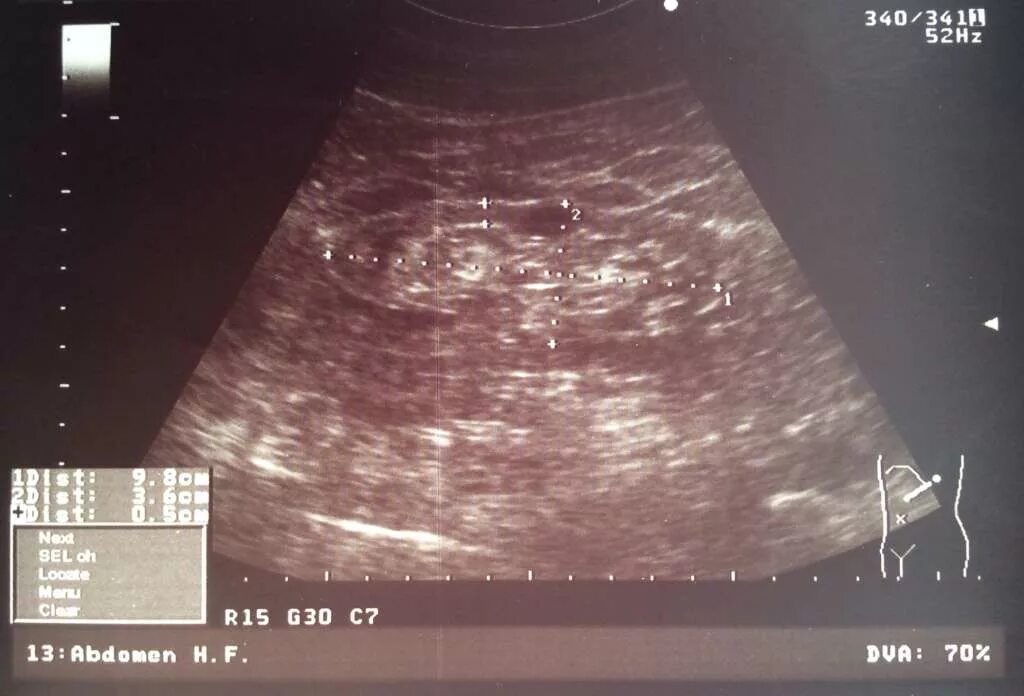

Нефросклероз почек на узи что это такое